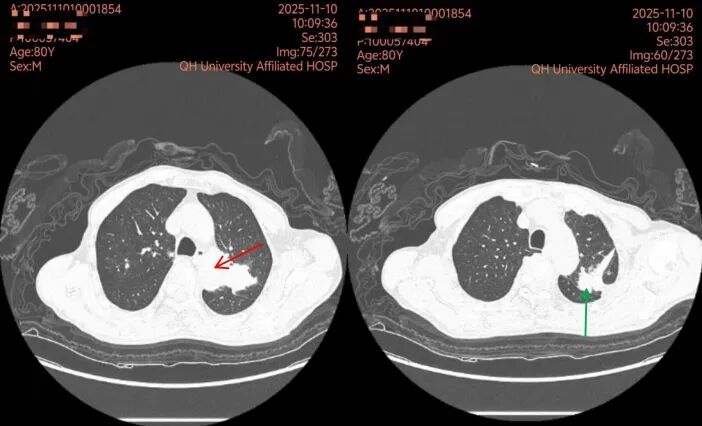

据悉,老人近半个月来反复出现胸口隐痛症状,左侧后背痛感尤为明显。经胸部CT检查,发现其左肺存在占位性病变,疑为肺癌,并伴有部分肺组织萎缩。此外,检查显示老人还存在慢性支气管炎、少量心包积液、血管增宽及胸椎骨折等问题。

为明确病因,徐徐与家属充分沟通后,决定为老人实施“经支气管镜肺活检”。这项技术通过一根细软的管子,从口腔或鼻腔进入气管,直达肺部病灶处取组织进行化验,具有创伤小、手术时间短、恢复快等优势。

检查过程很顺利,取出的组织经过化验,最终确诊是“肺腺癌”。困扰老人多日的胸痛原因,终于水落石出。